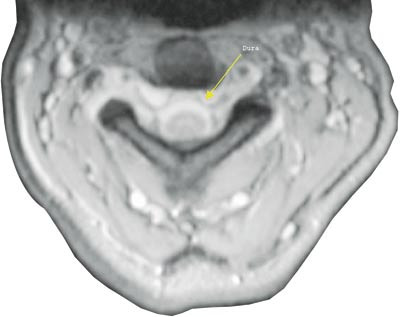

Pasient 1. Tidligere frisk 41 år gammel kvinne som fikk akutte smerter i nakke, hode og interskapulært mens hun syklet. Etter hvert fikk hun blikkfokuseringsvansker og diplopi. Ved innleggelse, 14 dager etter symptomdebut, hadde hun høyresidig abducensparese. Nevrologisk status var ellers normal. På direkte spørsmål angav hun smertefrihet om natten. MR med angiografi av intracerebrale kar viste ikke patologiske forhold, men det ble bemerket økt signal svarende til dura på de protonvektede bildene. Ved spinalpunksjon var det nødvendig å aspirere for å få ut væske. Diagnosen spontan intrakranial hypotensjon ble stilt på bakgrunn av klinisk bilde og null i spinalvæsketrykk. Cerebral MR med gadoliniumkontrast bekreftet diagnosen (fig 1). Det var også typiske funn ved MR av medulla, men det var ikke mulig å finne noe sikkert lekkasjepunkt (fig 2).

Typisk funn ved cerebral MR er diffus meningeal fortykkelse med gadoliniumkontrastopptak (5) – (9). Man tror dette skyldes dural vasodilatasjon og større konsentrasjon av kontrastmateriale i dural mikrovaskulatur og i interstitiell væske. Basis for denne antakelsen er den såkalte Monroe-Kellie-doktrinen, som sier at redusert spinalvæskevolum fører til kompensatorisk vasodilatasjon i hjerne og meninger (5, 8). Andre typiske MR-funn er tegn til nedfall av hjernen, forstørret hypofyse pga. hyperemi, subdural væskeansamling og forstørrede venesinuser (5, 8, 9). Spinal MR kan vise epidural væskeansamling med signal som spinalvæske, spinale hygromer, dilatasjon av cervikale epidurale vener og sammenfalt duralsekk (10) – (12).